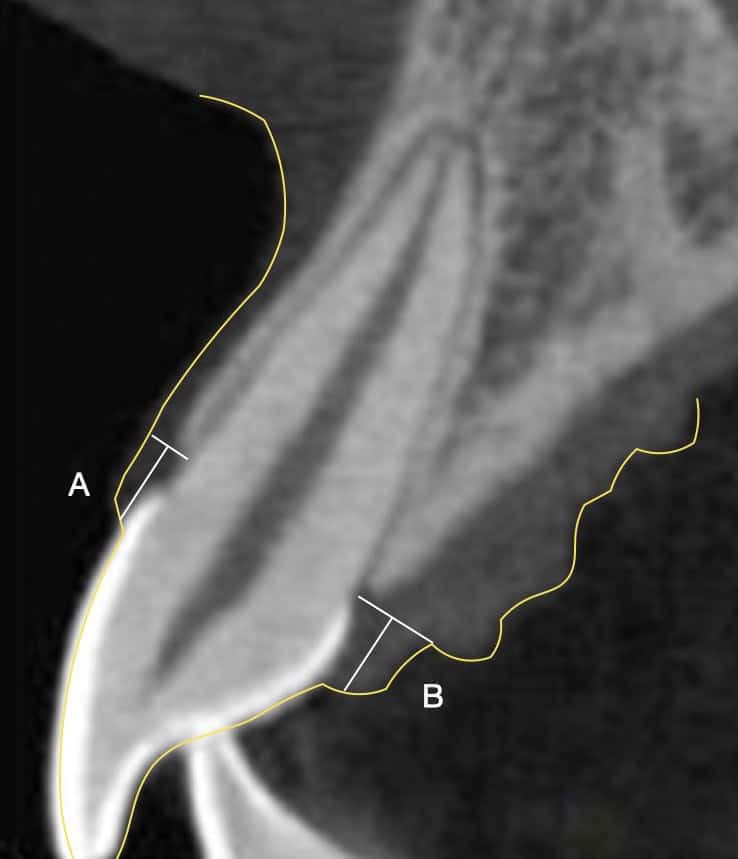

A townhowse of beautiful proportions:

Note the natural architecture of the periodontium, with a narrow base of the soft tissue at the margin of the bone and a longer dimension in height! This is especially pronounced at the buccal sites (A), but the base widens palatal (B) where the angle of the palatal alveolar ridge widens. Looks great, but don't try this with implants!